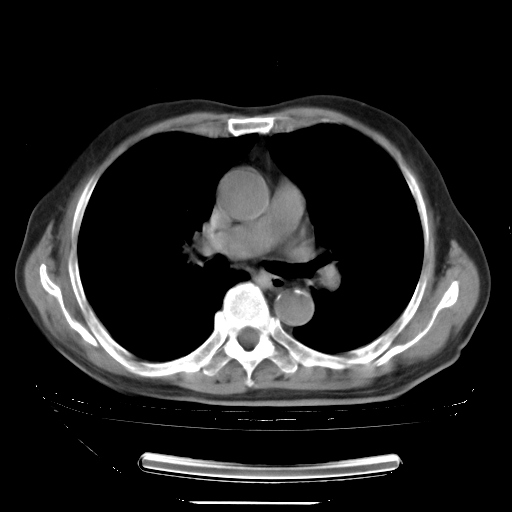

今天复查肺部CT,发现双肺广泛磨玻璃样改变。所以我把3月19日和5月9日相隔50天的肺部CT上传。请大家会诊。

5月9日肺部CT(在4月27日齐鲁医院肺部CT描述部分肺组织磨玻璃样改变,12天后肺组织广泛磨玻璃样改变)

大致读了系列胸部CT:纵隔窗无明显异常,肺窗:从4、27至今:主要是双肺中下野外带可见毛玻璃样改变,目前处于急性肺泡炎阶段,至于原因考虑1、结替组织或胶原血管性疾病所致?2、恶性疾病如恶组在肺部所致的表现或细支气管肺泡癌?3、药物或其它原因如肺蛋白沉着症所致肺泡炎目前不太可能?总之,明天就去请我院的呼吸科、感染科、血液科和临免专家会诊哈。